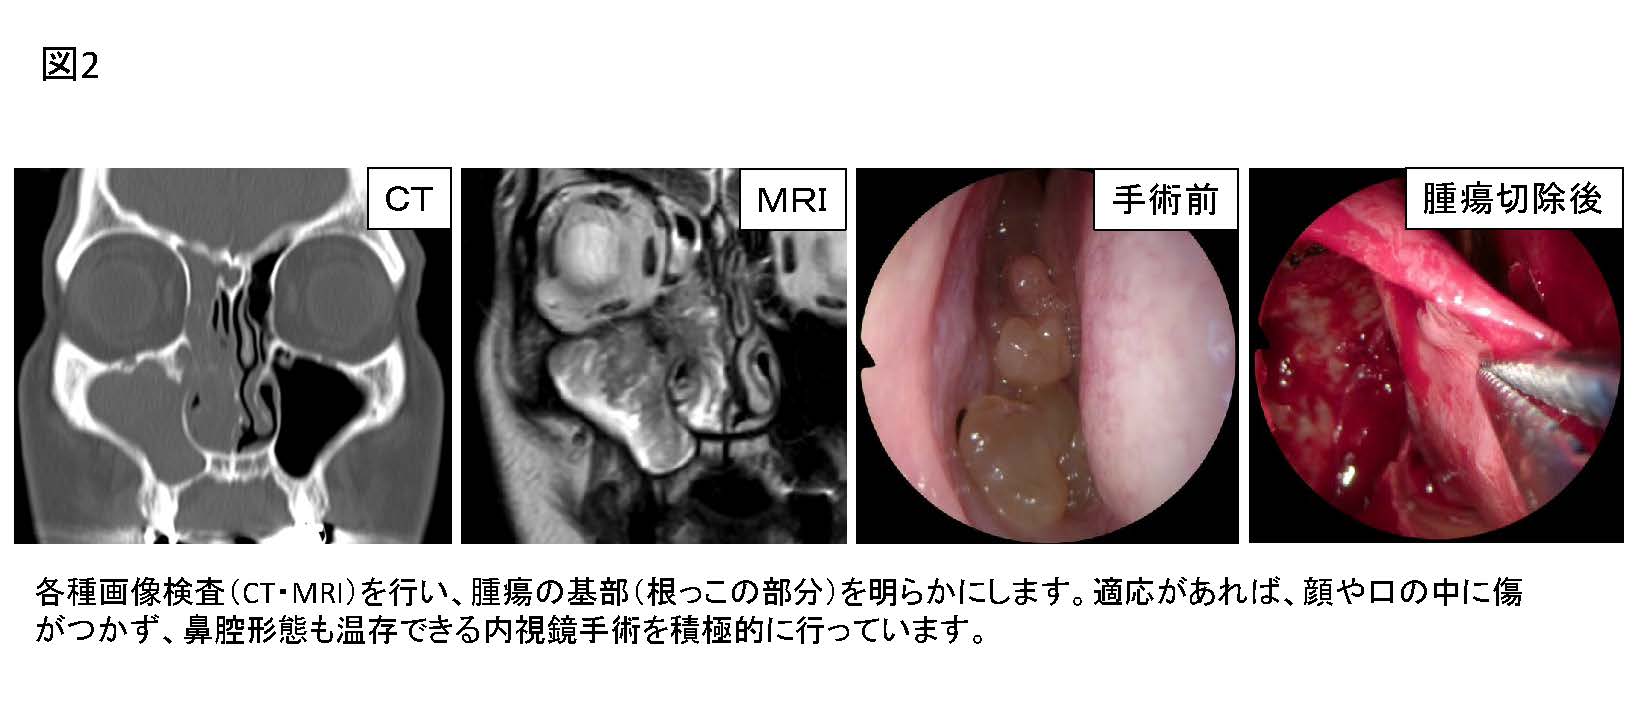

Ct検査よりがん組織と正常組織の区別が明確でct検査とは異なる情報からがんの深さや広がりリンパ節への転移の有無を調べます 7超音波エコー検査 首の表面から超音波をあ てそのはね返りをモニターで見ながら確認. 下咽頭癌の進展範囲を読影する際のチェックポイント 腫瘍の最大径 喉頭への進展の有無 軟骨浸潤の有無 上下方向への進展範囲の決定中咽頭頸部食道 軟部組織浸潤の有無特に梨状癌 梨状窩尖部への進展の有無.

中咽頭癌 ct. 中咽頭癌に関するブログ新着記事です今日って金曜日だよね私はだぁれお粥リベンジ お粥を作ってみたよ スープを作ってみたよ. Ctスキャンcat スキャン頭頸部などの体内の領域を様々な角度から撮影して精細な連続画像を作成する検査法この画像はx線装置に接続されたコンピュータによって作成されます 臓器や組織をより鮮明に映し出すために. 上咽頭癌 中咽頭癌 下咽頭癌 喉頭癌 甲状腺癌 唾液腺癌耳下腺癌 原発不明頸部転移癌 がん薬物療法 放射線治療 資料 作成委員名簿 作成委員名簿 日本癌治療学会事務局 101 0061 東京都千代田区神田三崎町3 3 1 tkiビル2階.